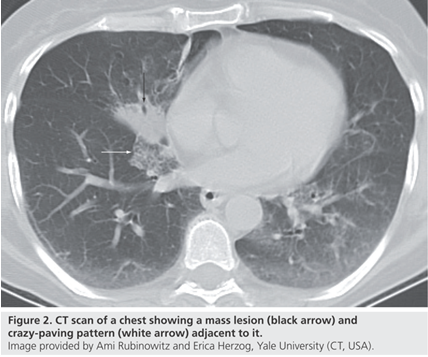

脂质性肺炎被认为由肺泡内含脂物质异物反应所致,脂质到达肺泡的机制:摄入(非挥发烃类)或吸入(挥发烃类),少数矿物油如汽油,即使经静脉注射也可导致肺损伤。在肺泡内,油脂乳化后被巨噬细胞吞噬,肺泡巨噬细胞不能代谢脂肪物质,当巨噬细胞死亡后油脂反复进入肺泡;油脂异常释放导致巨噬细胞肉芽肿反应、慢性炎症反应、肺泡及间隔纤维化;新鲜病灶显示肺泡被载脂巨噬细胞浸润,肺泡壁和间隔基本正常;进展性病灶显示巨大的空泡和肺泡壁、支气管壁和间隔炎性浸润,大量含脂空泡周围纤维化和实质破坏是晚期病变的特征。如果吸入矿物油或植物油,不易在体内分解,易在体内形成结节或肿块。如果吸入动物油,在体内可被分解为脂肪酸,导致炎症反应,局部肺水肿或肺出血。临床表现缺乏特异性,个体差异明显,从无症状到严重,甚至危及生命,常因患者年龄、吸入脂质的时间、数量及种类而不同。有症状的外源性脂质性肺炎常表现为慢性咳嗽或呼吸困难,其他表现为胸痛、咯血、间歇发热等。查体可发现叩诊浊音,听诊可闻及爆破音或干啰音。在长期持续进展性疾病患者中,体检可发现慢性缺氧,如杵状指。外源性类脂性肺炎可模拟许多其他肺部疾病,包括癌、肺炎、急性呼吸窘迫综合征和局部肉芽肿,HRCT最常见的表现是气腔实变、磨玻璃影、铺路石征、小叶间隔增厚、肿块样病变。急性外源性脂质性肺炎一般在吸入后半小时内出现肺部影像异常,大部分患者在24小时内出现肺部阴影,通常呈磨玻璃或实变影,一般在2周至8个月可逐渐改善或吸收,偶尔会遗留少许瘢痕纤维。慢性外源性脂质性肺炎最常见的影像学表现为一个或多个肺段的磨玻璃结节或实变影,通常在支气管周围分布,累及下叶最常见。实变可伴临近肺组织扭曲,在疾病晚期,由于油脂从肺泡内运送至肺间质,可出现增厚的小叶间隔或纤维化,还可见到铺路石征,也可表现为含脂质的结节或肿块影,由于慢性炎症及纤维化,肿块边界常不规则或有毛刺。下图为文献报道的一例急性外源性脂质性肺炎,患者胸部CT主要表现为实变,其中有液化坏死灶。下图为3例外源性脂质性肺炎患者的胸部CT,主要表现为肺结节/肿块和磨玻璃影。治疗3个月后,病变较轻者明显吸收。外源性脂质性肺炎的诊断主要基于暴露史,与疾病相符的影像学改变,唾液、支气管肺泡灌洗液或活检肺组织病理发现富含脂质的巨噬细胞,需要综合以上考虑诊断。支气管肺泡灌洗液的外观有提示价值,常为白色或浑浊液体,在表面可见脂肪漂浮层。